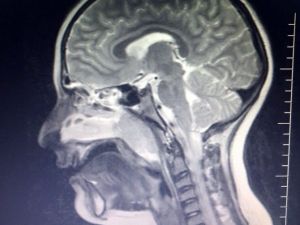

Geniz Eti Çocuklarda Uyku Ve Solunum Zorluğuna Yol Açıyor